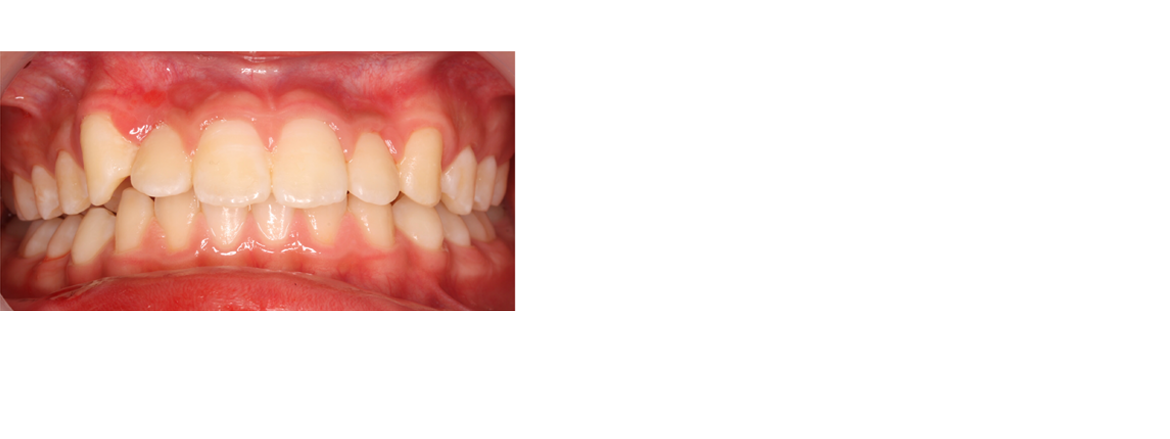

矯正用の拡大装置を使うと顎を広げる作用で歯並びも良くなりますが、鼻腔も広がるので口呼吸を改善し、様々な症状が改善する可能性があります。ぜひご相談ください。

硬いものをよく噛んでいれば顎が成長するのでしょうが、柔らかいものを食べている私たちは顎が小さくなっています。そこで歯列を大きくする拡大装置を使って歯列全体を大きくして永久歯が綺麗に並ぶように治療します。